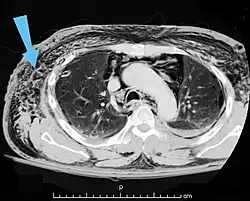

O enfisema pode produzir protuberâncias, como nódulos móveis com ruídos crepitantes a palpação. Em uma radiografia de tórax, o enfisema subcutâneo pode ser visto como estriações radioluzentes (escuras) nas áreas com músculos. O ar nos tecidos subcutâneos pode interferir na radiografia do tórax, potencialmente obscurecendo condições graves, como o pneumotórax. Também pode reduzir a eficácia do ultrassom.[8] Também é visível na tomografia e na ressonância magnética como bolhas escuras.